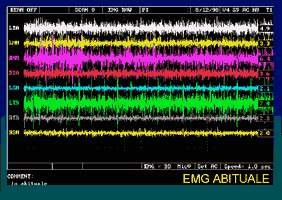

Fig. 6 Tipico rilassamento di Temporali e

Masseteri nel tempo, partendo dalla

situazione abituale e inserendo Aqualizer®.

È stata eseguita una lettura EMG di 2

secondi ogni minuto

Fig. 7 Situazione EMG con diversi

tipi di rilassamento: Abituale

Fig. 8 Situazione EMG con diversi tipi di

rilassamento: 45 minuti TENS su

Kerr Occlusal Indicator Wax

Fig. 9 Situazione EMG con diversi tipi di

rilassamento: dopo i 45 minuti si spegn

la TENS e viene applicato per

10 minuti Aqualizer®

NB - Le differenze di colore nei grafici, (fig. 6-7-8-9) servono esclusivamente ad evidenziare le escursioni degli istogrammi

Nei casi di miopatia e mioartropatia i risultati sono stati a dir poco lusinghieri: il riequilibrio di temporali e masseteri si otteneva in pochissimi minuti, mediamente 8, ed il livello di simmetria muscolare era pressoché perfetto (Foto 6), molto migliore di quello ottenibile con la T.E.N.S., fino ad oggi da noi riscontrato il migliore. Gli Pterigoidei erano meno dolenti alla palpazione in un tempo medio di circa 20 minuti, un dato in parte sovrapponibile ad una nostra precedente ricerca sui Jig (28), anche se questi ultimi appaiono più efficaci. Al test EMG al serramento si può sempre riscontrare la contrazione contemporanea dei quattro muscoli, analogamente a quanto succede con il test dei rulli di cotone, segno di una possibilità di appoggio equilibrato (29). Risulta inoltre significativo il quadro EMG a riposo in relazione al tipo di rilassamento introdotto. Nella foto 7 è monitorizzato lo status in abituale con forti asimmetrie, nella immagine successiva (foto 8) si evidenzia il ruolo svolto da 45 di TENS con risultati incerti: alcuni muscoli si sono certamente rilassati ma altri meno, provocando un divario maggiore e quindi uno squilibrio maggiore. Con l'utilizzo per 10 min. di Aqualizer‘ (foto 9) tutto diventa più omogeneo e soprattutto più equilibrato. Molto importante è, a nostro avviso, anche l’informazione kinesiografica ed EMG dello schema deglutitorio, infatti praticamente tutti i pazienti con deglutizione atipica o infantile correggono istantaneamente l'atto, per lo più eseguendo deglutizioni normali di tipo 1. Questo potrebbe costringerci a rivedere la effettiva necessità di una ginnastica miofunzionale correttiva della deglutizione, in presenza di patologia (30).